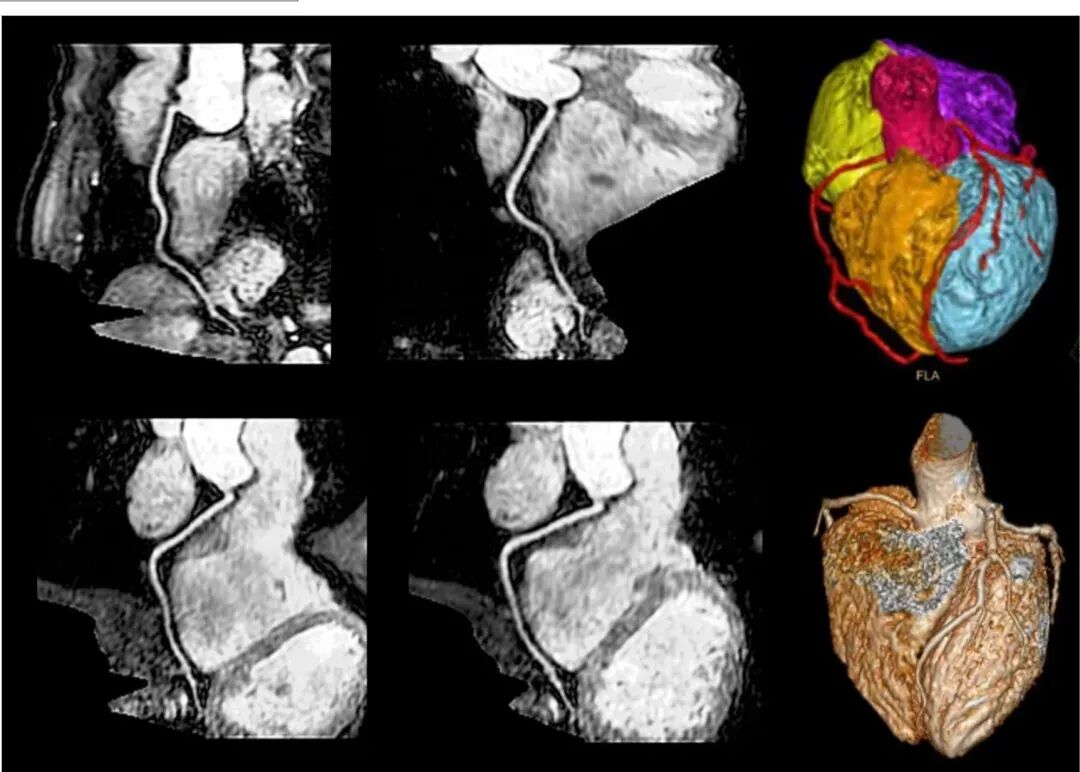

而磁共振血管成像技术(MRA)不仅无创无辐射,而且具有良好的分辨率和清晰度等优点,最重要的是,不需要打入“造影剂”即可对冠状动脉进行全面检查,在较早的时间发现冠脉病变、避免出现生命危险方面,具有无可替代的优势。自2018年开始,飞利浦便推出无创冠脉MR产品。

图片

飞利浦Ingenia Elition 3.0T磁共振图像分辨率更高,成像更清晰,对心血管系统、中枢神经系统,骨关节,肌肉等系统的疾病检查最具优势,有利于捕捉到微小病灶,提高病灶检出率,为疾病的早期诊断提供依据,尤其心脏磁共振可以18S不打药3D冠脉成像,心脏造影及功能成像采用压缩感知技术,成像速度和成像质量都有很大提升,对临床诊疗具有重大帮助。